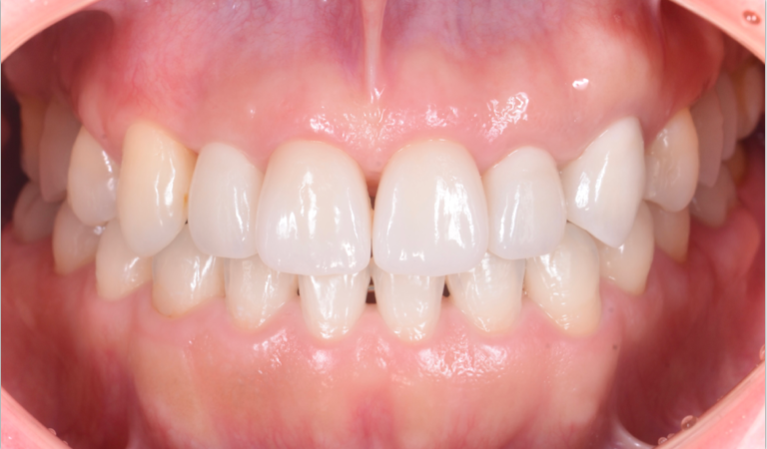

機能と審美性の回復を目指す総合治療

重度の歯周病になると咬合崩壊を起こしてしまう場合があります。その場合、歯周病治療のみならず、矯正治療・不良補綴物のやり直し・インプラントなど様々な治療を組み合わせて機能の回復を目指す必要があります。また失った審美性の回復も同時に目指すことで、治療後に口元を気にする必要がなくなります。

重度歯周病の症例